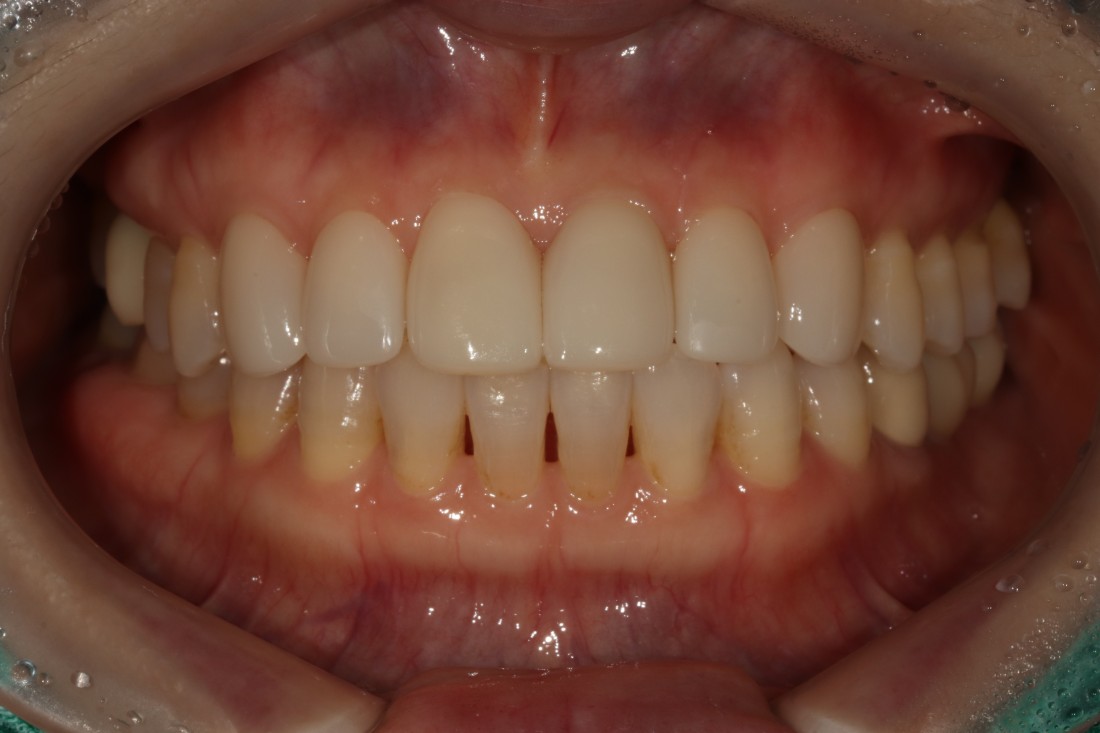

누가봐도 라미네이트 한 것 같은

뭉툭하고 새하얀 치아가 아니라,

광주 무삭제 라미네이트 치과는

'자연스러운 아름다움'을 추구합니다.

그렇기 때문에 20대부터 60대까지

정말 다양한 연령대의 고객님들이

지인 추천으로 방문해주시고 계신데요.

단순히 예뻐지기 위함이 아니라,

앞니 컴플렉스를 해결하고

치아의 기능적 요소까지 생각하여

불편함 없는 라미네이트 진료를 위해

노력하고 있습니다.